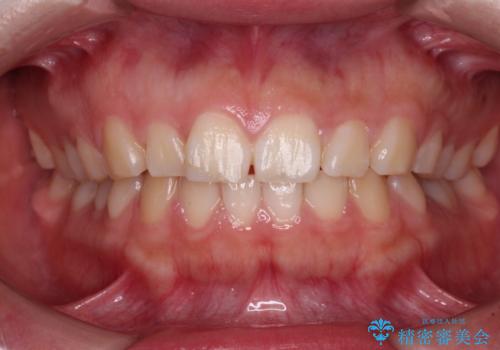

- 出っ歯と口の閉じにくさ、デコボコを気にして来院された患者様です。

口元の突出感を改善するため、上下左右第一小臼歯4本の抜歯を行い、ワイヤー装置による矯正治療を行うこととしました。

抜歯矯正を行ったことで、顎先のつっぱり感や口元の閉じにくさを解消することができました。